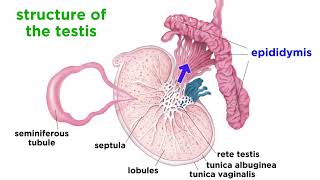

27. The Reproductive System

Anatomy of the Male Reproductive System

Male Reproductive structures